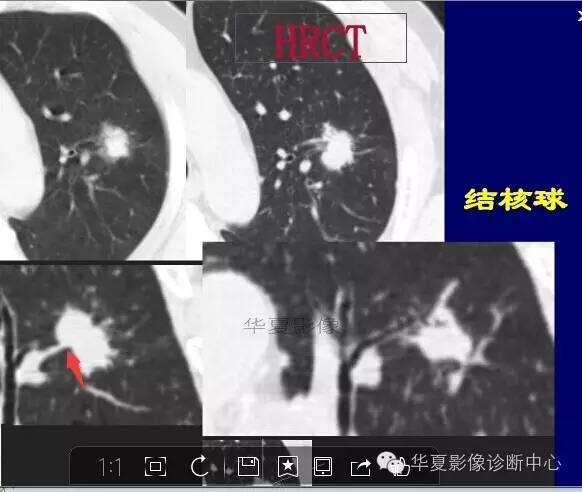

这一例是否GGO成分几乎没有

基本是实性的

那就按实性的分析

磨玻璃结节良恶性影像分析策略 都是支气管

磨玻璃结节良恶性影像分析策略

胸膜凹陷,分叶征